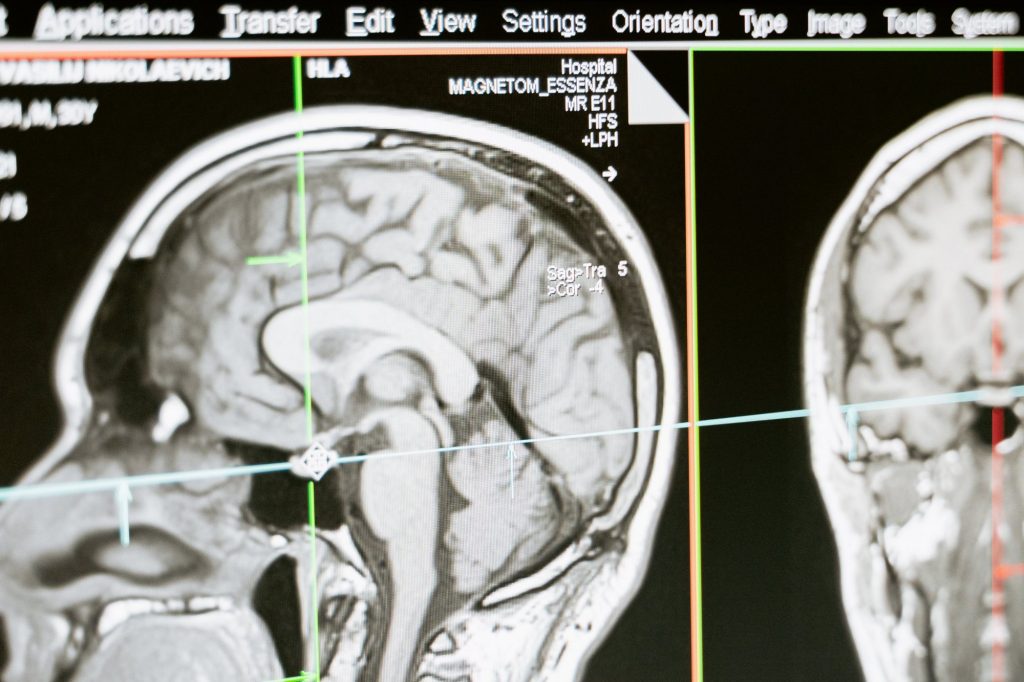

Σήμερα, η Αλτσχάιμερ μπορεί να ανιχνευτεί στο προσυμπτωματικό στάδιο με τομογραφίες εγκεφάλου που εντοπίζουν παθολογικές αποθέσεις μιας πρωτεΐνης που ονομάζονται βήτα αμυλοειδές. Η εξέταση όμως είναι ακριβή και συχνά δεν καλύπτεται από τα ασφαλιστικά ταμεία.